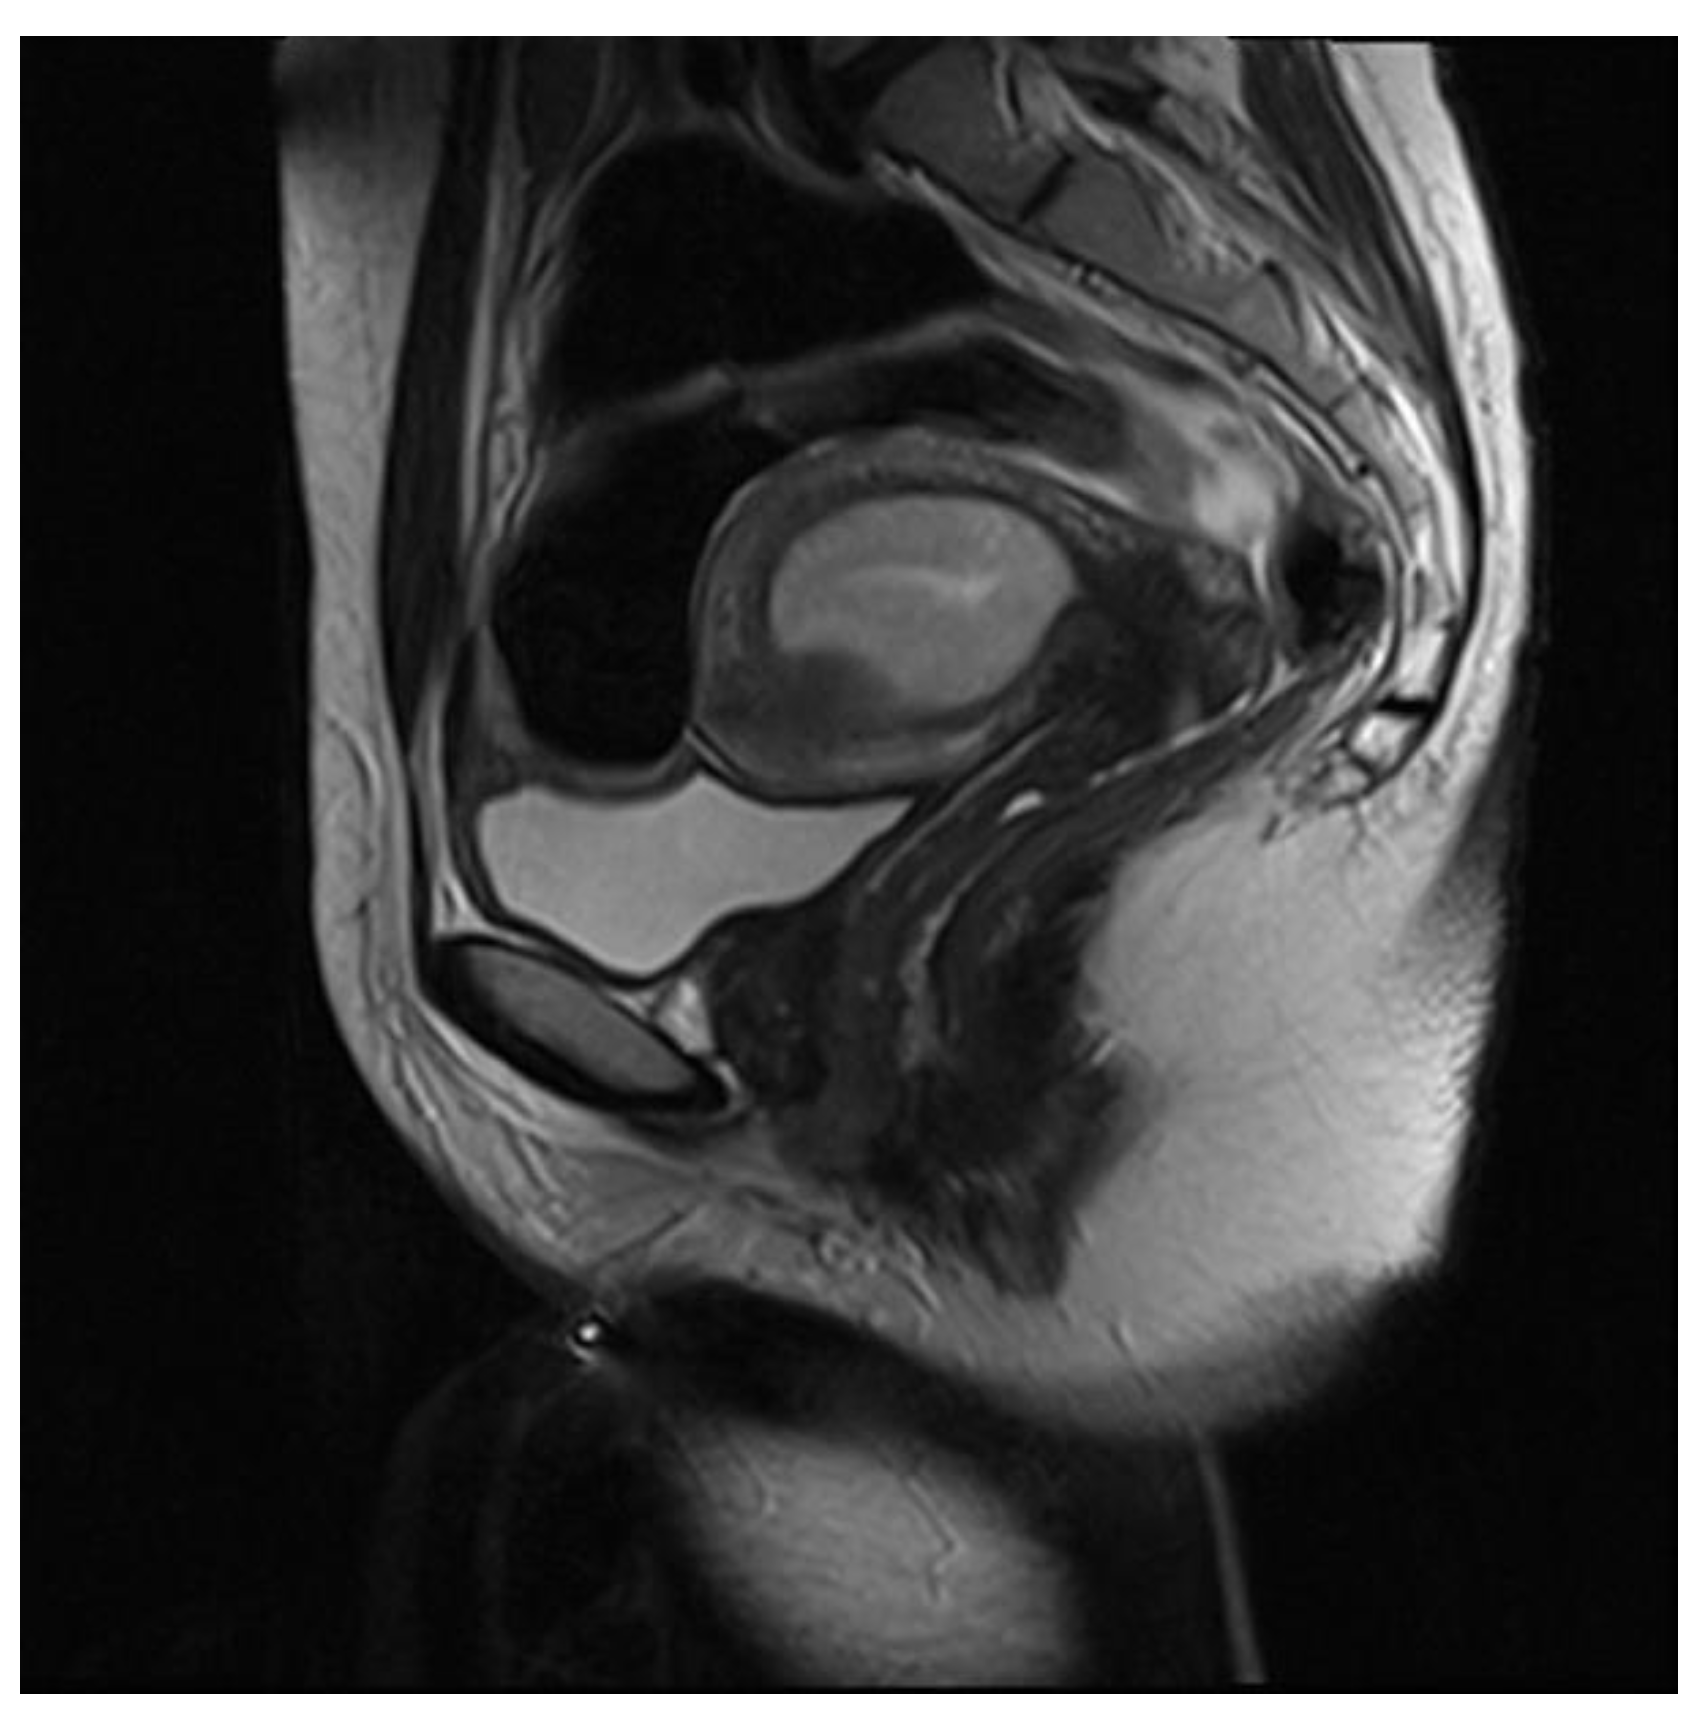

3.3.3. Adenomyoma

3.4. Pitfalls